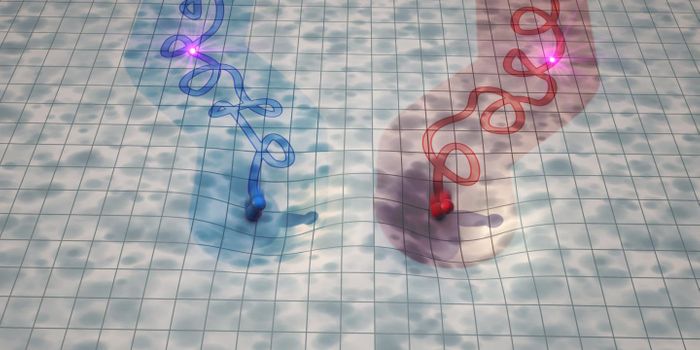

OCT 29, 2018NeuroscienceNerve regeneration by electrical stimulation